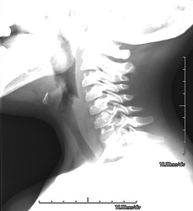

Tècnica que usa els raigs X a través de la qual s'obtenen imatges del càvum per al seu estudi. Indicacions: dificultat respiratòria, angines de repetició en lactants i nens - RX Columna cervical

Tècnica que usa els raigs X a través de la qual s'obtenen imatges de la columna cervical per al seu estudi. Indicacions: traumatisme, contractura cervical, dolor articular. - RX Ossos propis nasals

- RX Columna cervical

Tècnica que usa els raigs X a través de la qual s'obtenen imatges de la columna cervical per al seu estudi. Indicacions: traumatisme, dolor cervical. - RX Columna dorsal

- RX Càvum

Tècnica que usa els raigs X a través de la qual s'obtenen imatges del càvum per al seu estudi. Indicacions: dificultat respiratòria, regurgitació, otitis de repetició. - RX Edat òssia